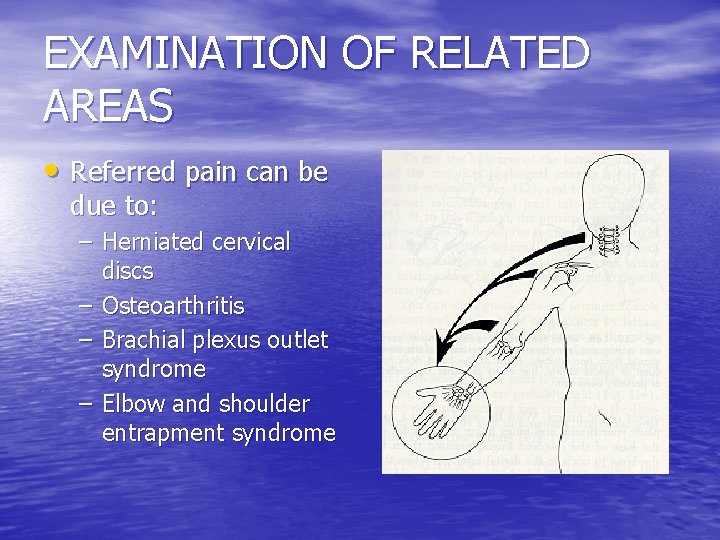

EXAMINATION OF RELATED AREAS • Referred pain can be due to: – Herniated cervical discs – Osteoarthritis – Brachial plexus outlet syndrome – Elbow and shoulder entrapment syndrome